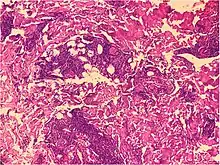

| Prevesicular stage of bullous pemphigoid | Image at right shows influx of inflammatory cells including eosinophils and neutrophils in the dermis (solid arrow) and blister cavity (dashed arrows), and deposition of fibrin (asterisks).[15] However, the diagnosis of bullous pemphigoid consist of at least 2 positive results out of 3 criteria:[19]

|

![]() |